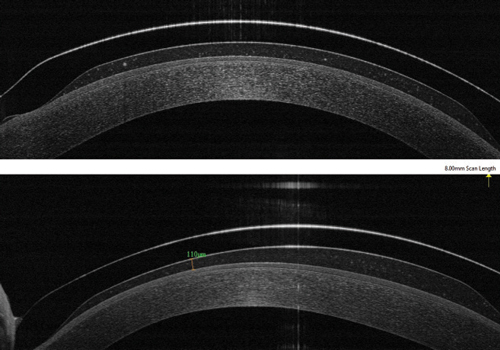

Lentes esclerales: la importancia del vault